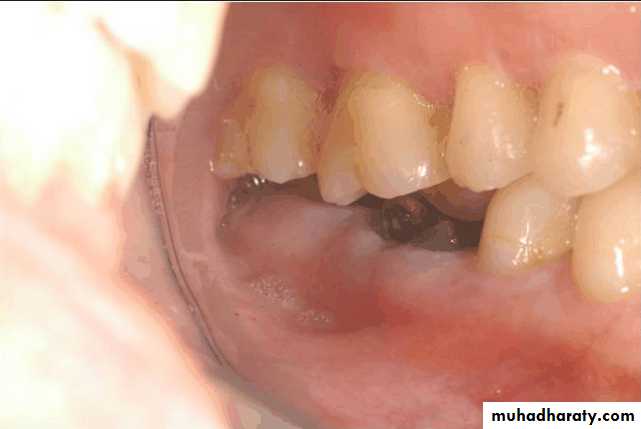

• Treatment over erupted teeth

• If the tooth is extruded above the occlusal plane because of lack of an antagonist –• Treatment

• Moderately extrude tooth – aprox 2mm - enameloplasty.

• If the extrusion is greater than 2 mm or if the tooth does not lend itself to enameloplasty, the placement of a crown is indicated.

• If size of pulp prevent the required tooth reduction endodontic therapy

• If clinical crown length is inadequate crown lengthning

• Orthodontic treatment

• Severely extruded teeth – contacting the opposing ridge & if alveolar bone followed eruption remove the tooth and recontour the bone is necessary

Occlusal plane

Occlusion plane may be irregular because of extrusionOne or more unopposed teeth.

Such conditions require corrective procedures if an acceptable occlusion is to be developed.